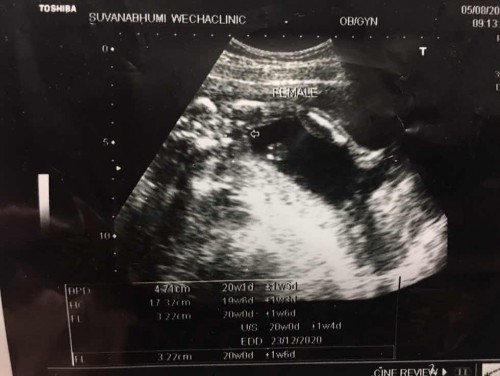

ซาวตอน20วีค

เเม่ๆลองช่วยทายหน่อยค่ะ ว่าชายหรือหญิง☺️

Female เพศ ญ ค่ะ ไม่ต้องทายแล้วววว 😁

ไม่ต้องเดาเลยแม่ Female มาเต็มๆ 😂

หมอก็เขียนอยู่งัยคะว่า Female

ในภาพหมอก็ระบุหนิค่ะว่า ญ